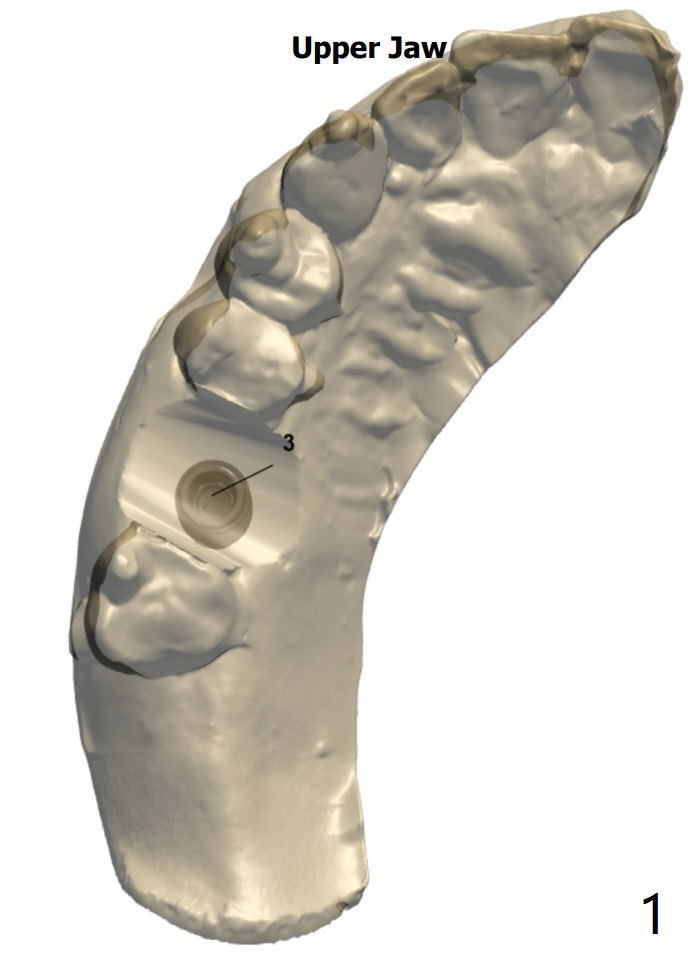

虽然病人骨头宽,但是右上6颊侧骨板薄(图二,三),准备外科手机,切断牙齿,分根拔除。IS dummy implant 4.5x10 and Treatment planning kit to determine the cuff height.